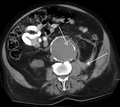

An axial contrast-enhanced CT scan demonstrating an abdominal aortic aneurysm of 4.8 by 3.8 cm